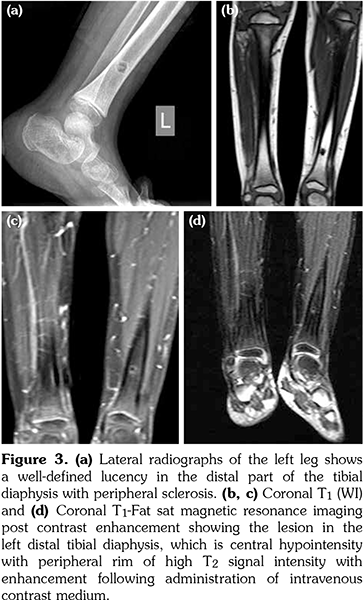

He was started on non-steroidal antiinflammatory drugs (NSAIDs), naproxen, and elemental iron. His fever and joint pain subsided after two weeks. However, two weeks later, he started complaining of pain in the lower end of the left tibia. Three-phase bone scan showed increased tracer uptake in the distal metaphysis of the left tibia in all phases, including flow phase, blood pool, and delayed phase (Figure 2). Plain X-ray of the left leg revealed a well-defined lucency in the distal part of tibial diaphysis with peripheral sclerosis (Figure 3a). Magnetic resonance imaging (MRI) of the left leg revealed a lesion in the left distal tibia diaphysis, which appeared as a central hypointensity with a peripheral rim of signal intensity, with enhancement following administration of intravenous contrast medium (Figure 3b-d). Open bone biopsy of the lower end of the left tibia revealed viable compact bony trabeculae with fibrosis and congestion in the marrow spaces. Features were of periosteal proliferation and were consistent with chronic osteomyelitis (Figure 4). Bone aspirate culture was negative.